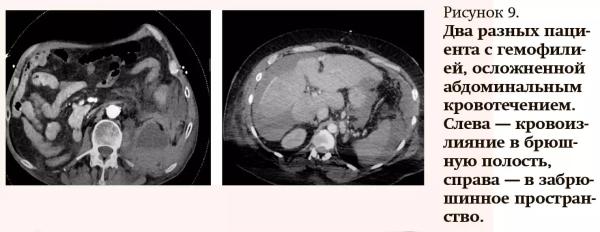

Причинами абдоминальных кровотечений могут быть различные травмы (не только в области живота, но и грудной клетки), острая и хроническая патология внутренних органов, состояния, связанные со снижением свертываемости крови (например, гемофилия), также это могут быть осложнения после хирургических вмешательств в постоперационном периоде. Чаще встречаются кровоизлияния в брюшную полость, гораздо реже — в забрюшинное пространство (см. рис. 9).